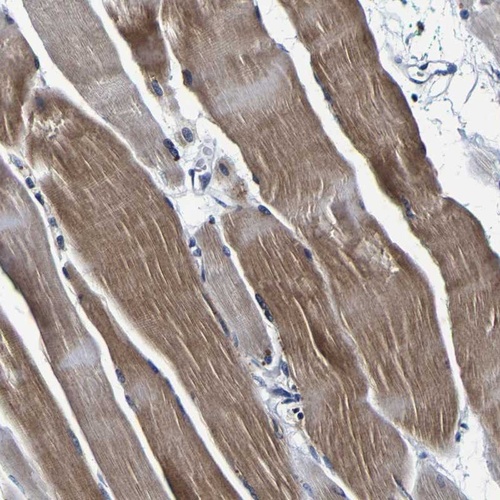

Immunohistochemical staining of human skeletal muscle shows moderate cytoplasmic positivity.